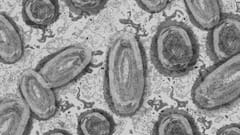

As New MPox Strain Spreads, Bustling Gold-Mining Town In Congo Emerges As Hotspot: Report